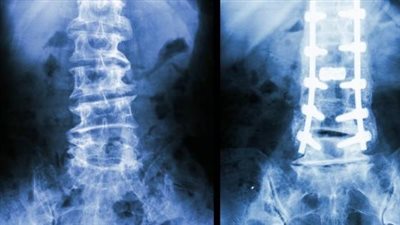

كشفت نتائج دراسة حديثة، أجراها علماء من جامعة سيدني، أن المواد الأفيونية ليست أكثر فعالية من العلاج الوهمي لعلاج آلام الظهر والرقبة الحادة، بل وربما تشكل خطرًا، ويرى الباحثون أنه يجب تحديث إرشادات العلاج لتنصح بعدم استخدام المواد الأفيونية لهذا النوع من الألم.

وأظهرت النتائج، أن المواد الأفيونية المستخدمة في الأدوية المسكنة لالام العظام وخاصة الرقبة والظهر، تتسبب في العديد من الأثار الجانبية، وقد تكون أكثر أنواع العلاجات خطورة، وهذا ما يتطلب تعديل الإرشادات الخاصة بهذه الأدوية.

وخصص الباحثون، المشاركين الذين يعانون من آلام حادة مفاجئة وقصيرة المدى في الظهر أو الرقبة بشكل عشوائي لدورة مدتها ستة أسابيع من المواد الأفيونية الموصوفة عادة أو الدواء الوهمي، وتلقت كلا المجموعتين أيضًا رعاية قياسية بما في ذلك النصائح لتجنب الراحة في الفراش والبقاء نشطين، وتمت متابعة المشاركين لمدة 52 أسبوعا.

وكشفت نتائج الدراسة، بعد 6 أسابيع، عن أنه لم يحصل أولئك الذين تلقوا المواد الأفيونية على تخفيف أفضل للألم مقارنة بأولئك الذين تناولوا الدواء الوهمي، كما أن أولئك الذين تلقوا المواد الأفيونية أصبحوا معرضين لخطر الإصابة بالمضاعفات الصحية والآثار الجانبية.